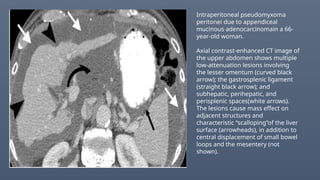

Intraperitoneal pseudomyxoma

peritonei due to appendiceal

mucinous adenocarcinomain a 66-

year-old woman.

Axial contrast-enhanced CT image of

the upper abdomen shows multiple

low-attenuation lesions involving

the lesser omentum (curved black

arrow); the gastrosplenic ligament

(straight black arrow); and

subhepatic, perihepatic, and

perisplenic spaces(white arrows).

The lesions cause mass effect on

adjacent structures and

characteristic “scalloping”of the liver

surface (arrowheads), in addition to

central displacement of small bowel

loops and the mesentery (not

shown).

Intraperitoneal pseudomyxoma peritonei dueto appendiceal mucinous adenocarcinomain a 66- year-old woman. Axial contrast-enhanced CT image of the upper abdomen shows multiple low-attenuation lesions involving the lesser omentum (curved black arrow); the gastrosplenic ligament (straight black arrow); and subhepatic, perihepatic, and perisplenic spaces(white arrows). The lesions cause mass effect on adjacent structures and characteristic “scalloping”of the liver surface (arrowheads), in addition to central displacement of small bowel loops and the mesentery (not shown).